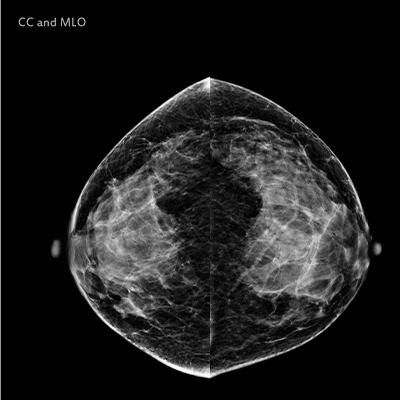

La Mammographie

Une mammographie est une radiographie des seins. Elle a pour but principal la détection du cancer mammaire à un stade précoce (le cancer du sein est le premier cancer chez la femme). Actuellement les mammographies sont entièrement numérisées.

Les images sont réalisées dans un mammographe par une manipulatrice en radiologie, en position debout, torse nu. Pour obtenir des images de qualité et réduire la dose d’irradiation, il est indispensable de réaliser une compression du sein. Chaque sein est comprimé de façon successive dans le sens haut-bas et selon un axe oblique. Ceci n’est pas douloureux. Vous avez la possibilité de discuter avec la manipulatrice en radiologie au cours de l’examen.